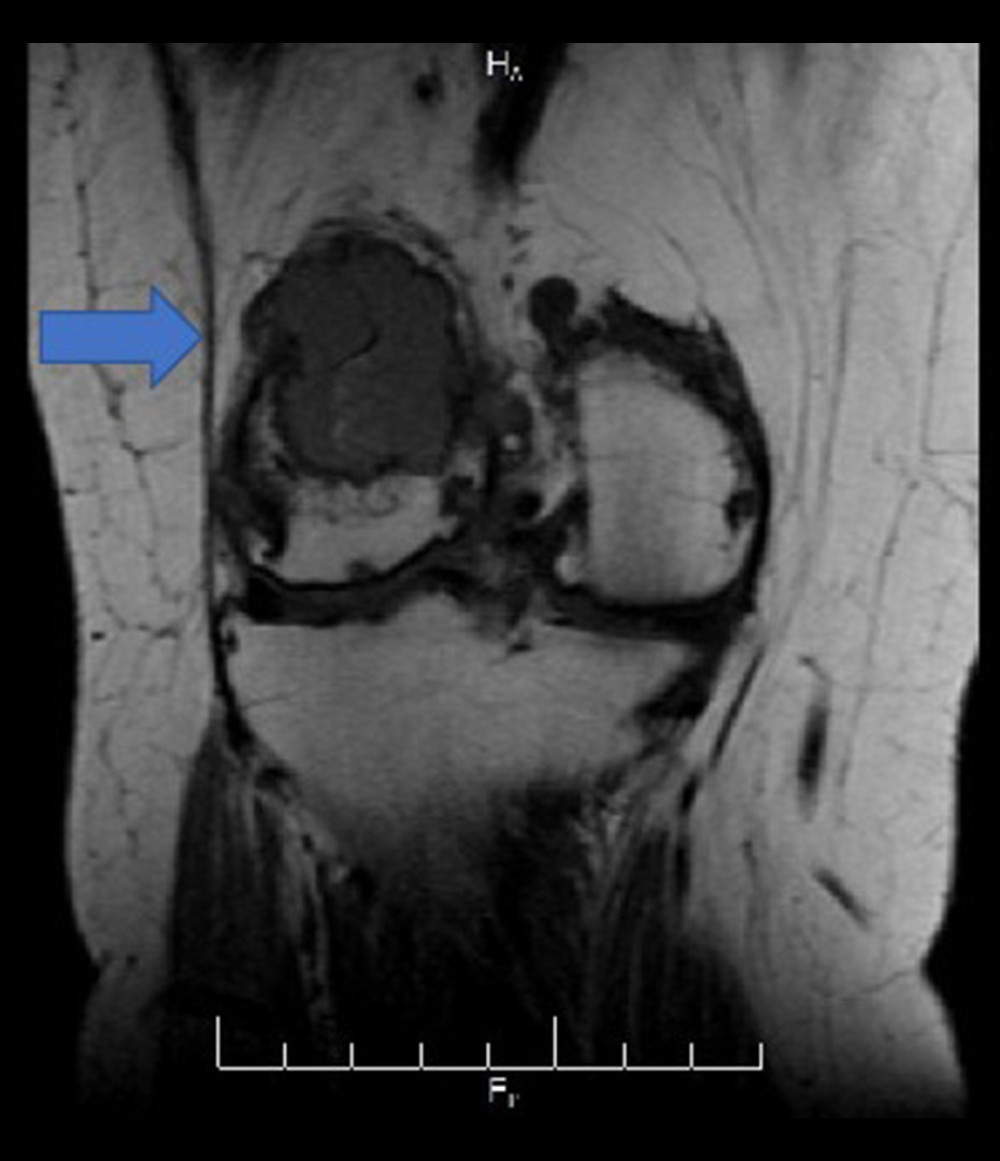

from amjcaserep.com

American Journal of Case Reports Knee Pain and Limping as Presenting